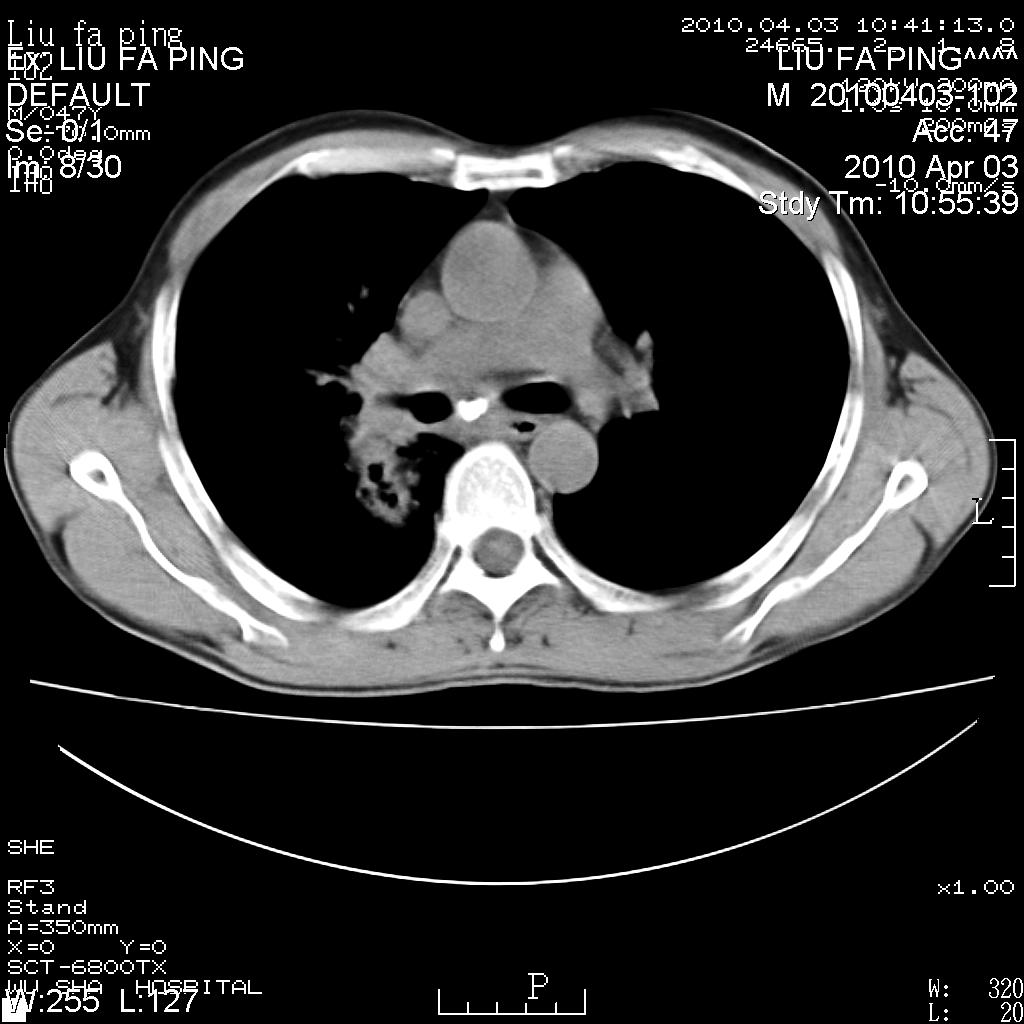

标题: CT25875:咳嗽数天。 [打印本页]

标题: CT25875:咳嗽数天。

平时身体健康,无不适

男性47岁,考虑中心性肺癌合并阻塞性肺炎,纵膈淋巴结肿大。肺内及纵膈淋巴结钙化。

建议支气管镜检

支持右侧中央型肺癌伴右肺上叶阻塞性炎症,建议纤支镜检查!

支持右侧中央型肺癌伴右肺上叶阻塞性炎症、纵膈淋巴结转移,建议纤支镜检查!

男性47岁,考虑中心性肺癌合并阻塞性肺炎,纵隔淋巴结肿大。肺内及纵隔淋巴结钙化。

考虑右肺中央型肺癌并阻塞性肺炎,右肺门及纵隔淋巴结转移;建议必要时行纤支镜检查进一步明确诊断。